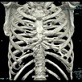

また立体再構成により骨の観察も可能です。

胸部横断面像 胸部冠状断面像 胸部肋骨立体像